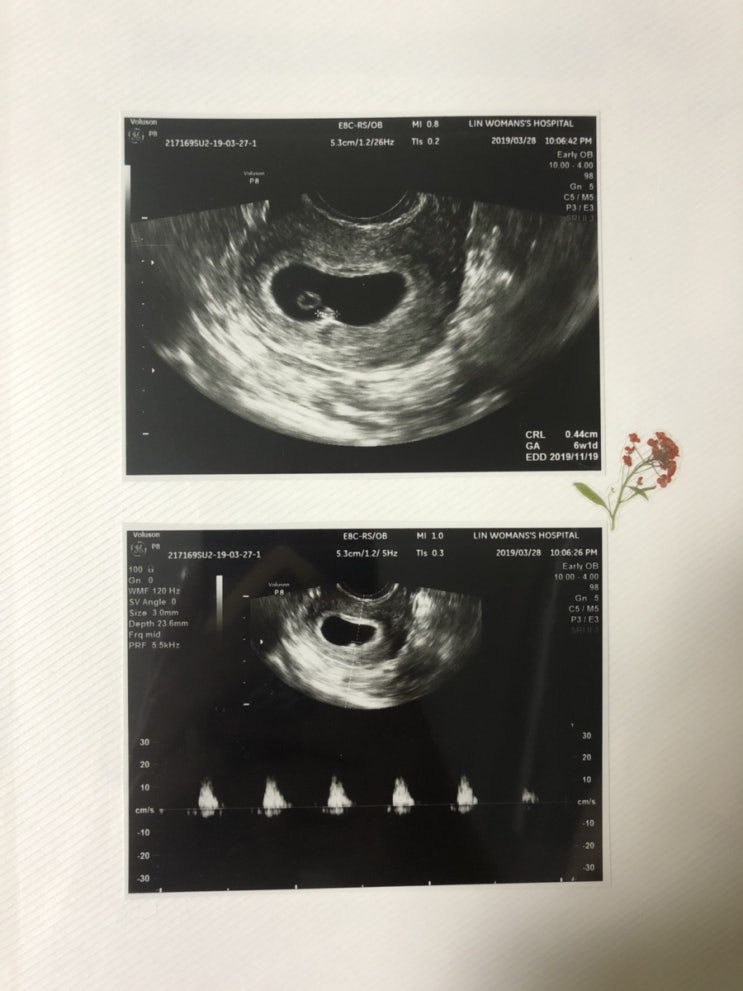

임신 5주, 임신 6주 증상 - 이유없는 피비침, 심장소리

/ 임신 5주, 임신 6주 - 이유없는 피비침, 심장소리 / 아기집과 난황까지 확인 후, 다음 진료때까지 설레며...